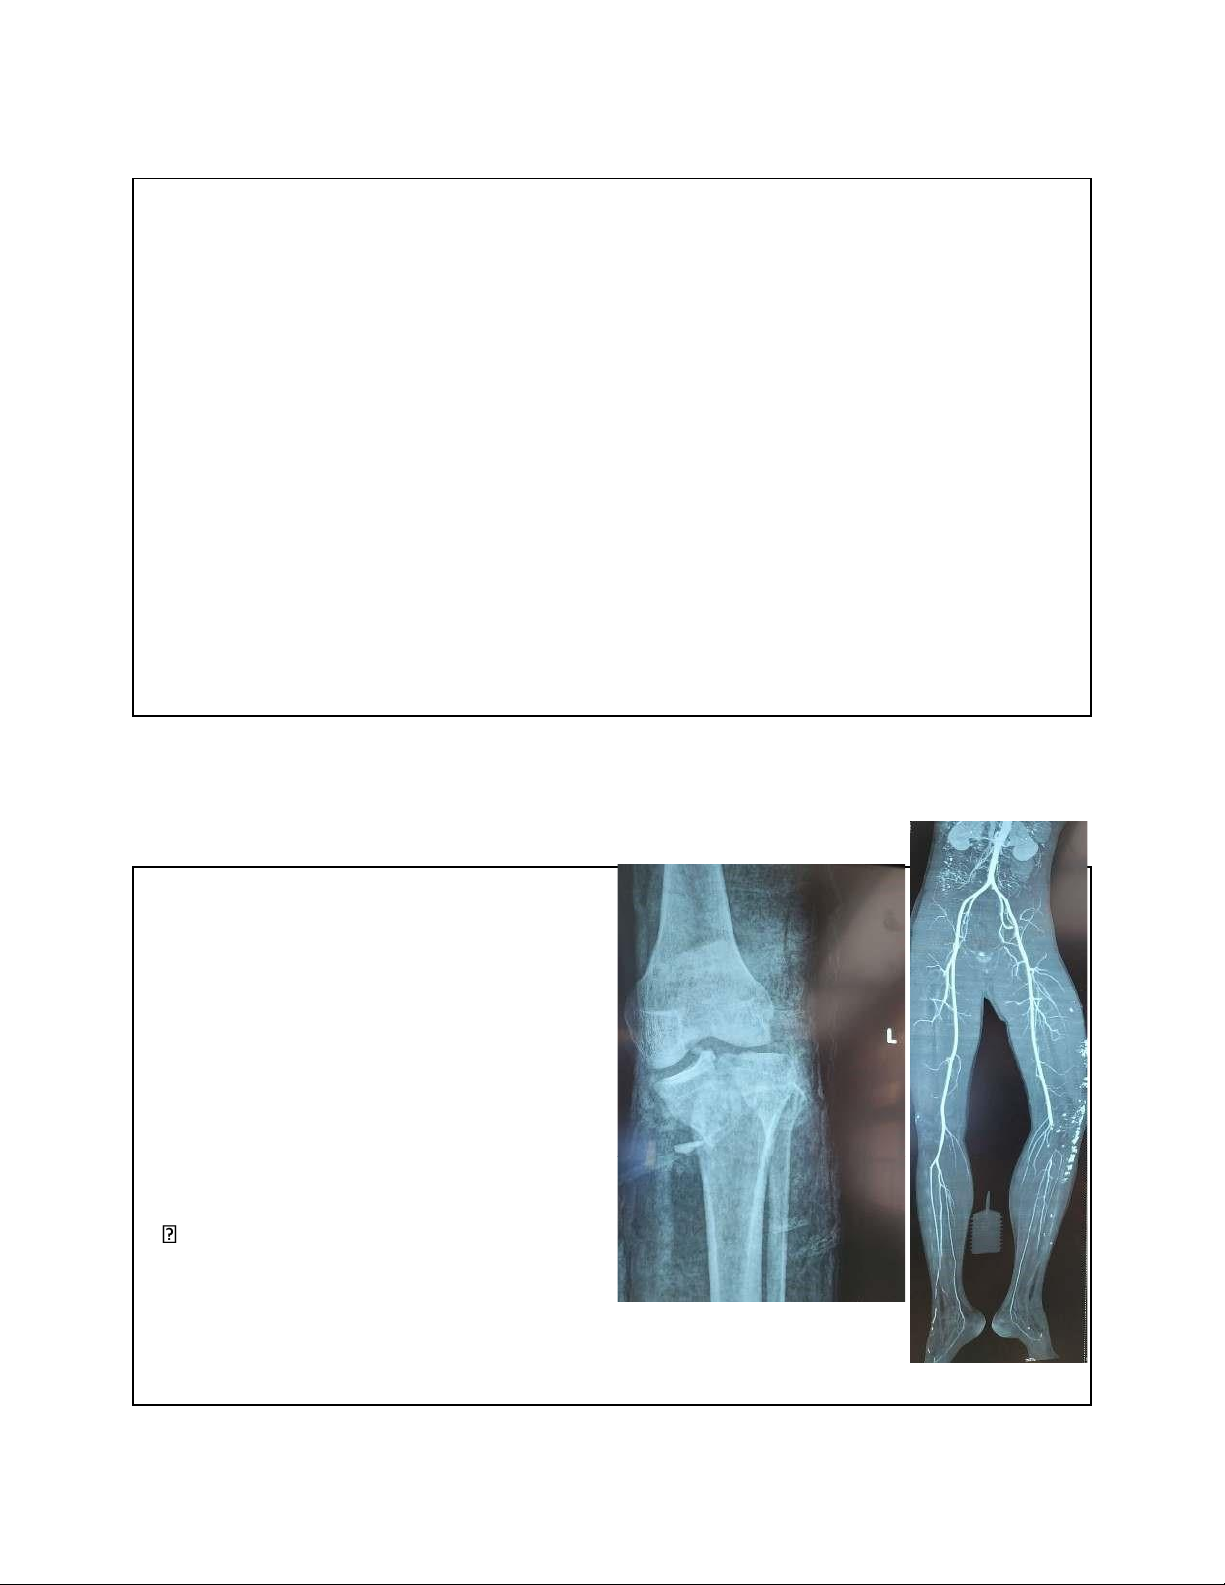

Nguyên nhân không chấn thương • Thoái hóa khớp • Viêm khớp • Viêm iểm bám tận của gân • U bướu • Nhiễm trùng 5 1. GÃY XƯƠNG

• Gãy xương vùng gối là chấn thương nguy hiểm

• Cần thăm khám kĩ ể chẩn oán sớm và iều trị kịp thời • Đặc biệt là: 1. Tổn thương mạch 2. Chèn ép khoang cứu ược chi, cứu mạng Can

thiệp: Mổ KHX và phục hồi lưu thông